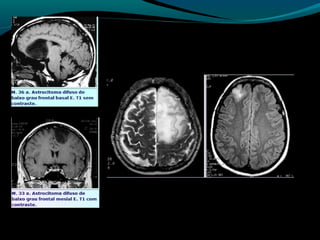

Astrocitoma difuso (GRAU II OMS)

Bem diferenciado;

Grau II;

10 a 15% dos astrocitomas;

Entre 20 a 45 anos;

Crescimento lento;

Tendência para degeneração maligna;

2/3 supratentoriais (frontal e temporal);

Convulsão e cefaléia;

Grau II, tendência à progressão para astrocitoma

anaplásico;

TC:

lesão hipo ou isodensa;

Geralmente NÃO se impregna por contraste ( se sim,

pensar em degeneração maligna);

RM:

Aspecto aparentemente circunscrito mas tumor se

infiltra;

Hipointenso em T1 e hiper em T2 e FLAIR;

Realce pelo Gd no tumor ou leptomeninge  pensar em

degeneração maligna;

Discreta redução do NAA;

Aumento do Co;

Aumento da relação Mi/Cr;

Valores do coeficiente de difusão aparente aumentados;

Baixa perfusão;

Recomendações:

RM associada às técnicas (ERM, difusão, perfusão)

método de escolha para detecção, controle evolutivo,

e controle pós-operatório;